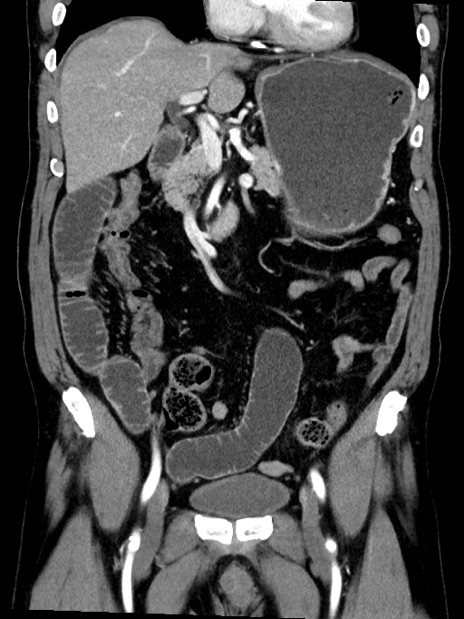

症例35(冠状断像)

【症例】70歳代 男性

【主訴】腹部膨満、嘔吐

【現病歴】昨日より腹部膨満感出現。本日増悪し、仙痛出現。嘔吐あり、受診。

【既往歴】糖尿病、胆摘後

【身体所見】BP 149/80mmHg、HR 74/min、BT 35.9℃、腹部:膨満、軟、圧痛なし。腸雑音減弱あり。上腹部正中切開瘢痕あり。

【データ】WBC 13500、CRP 1.72